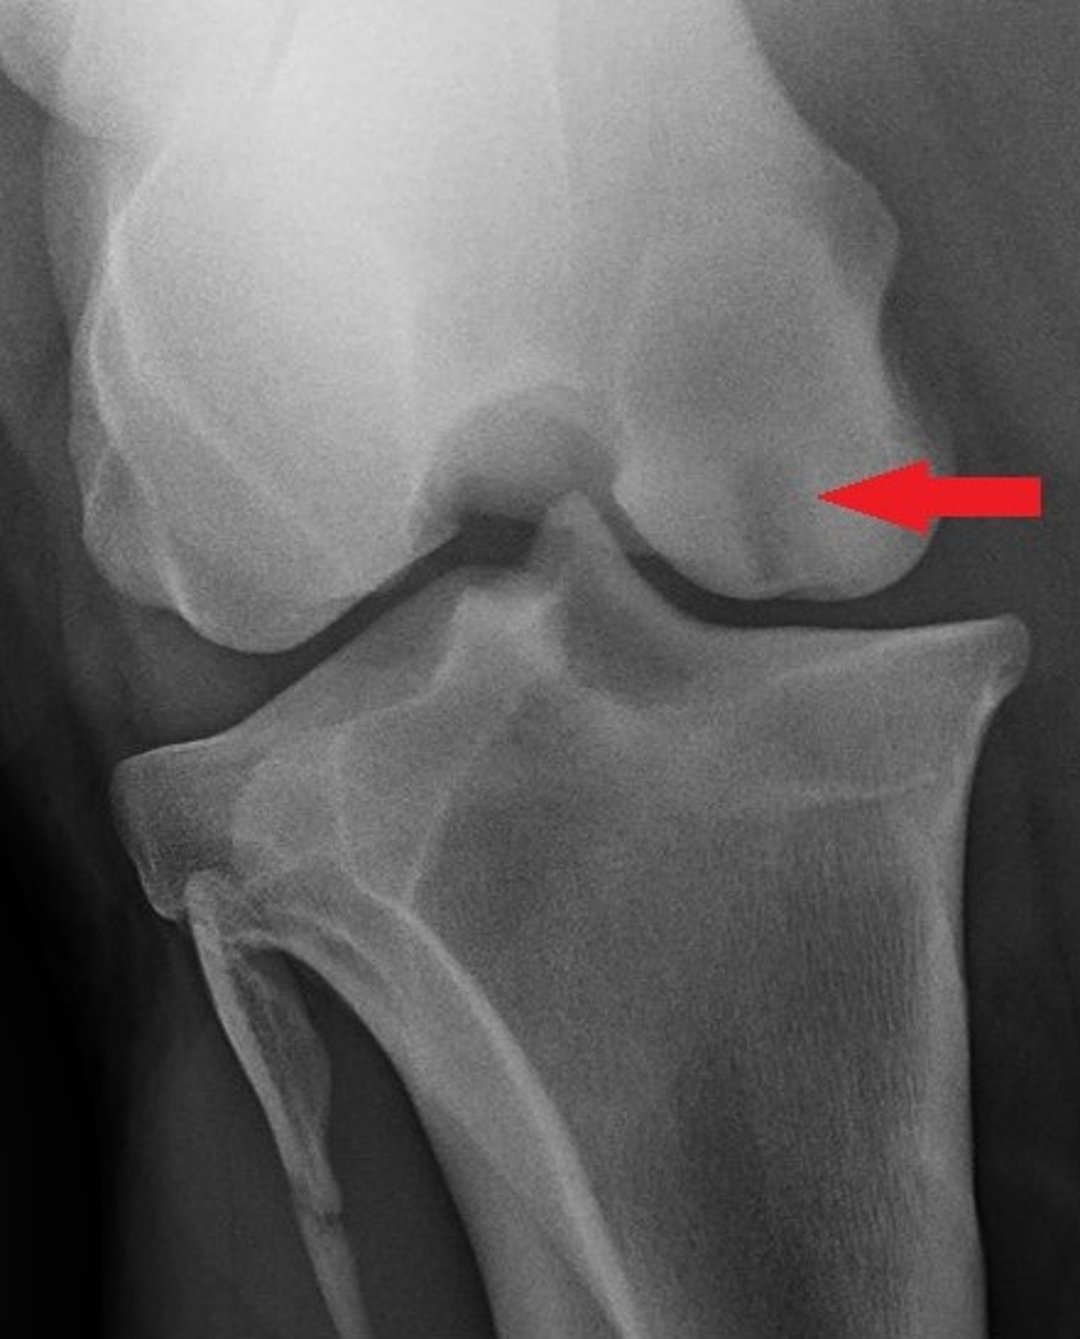

Caudal-cranial radiograph of the stifle of a horse, showing a subchondral bone cyst (arrow) at the medial femoral condyle.

Courtesy of Dr. Sushmitha Durgam.